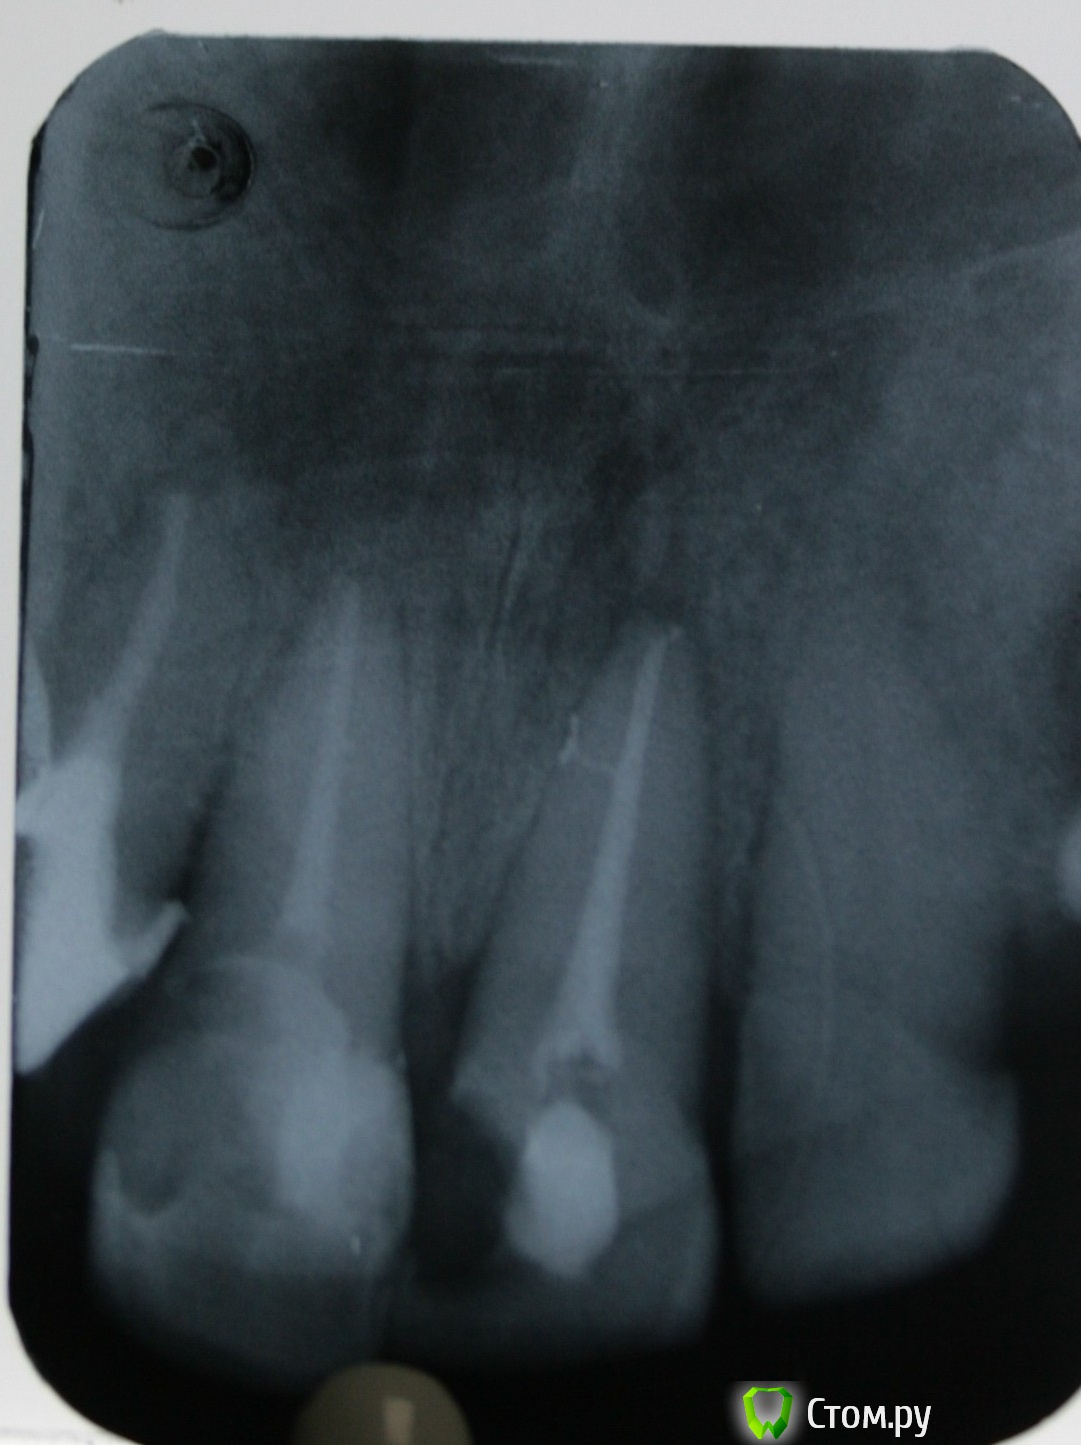

St. Опубликовано 7 ноября, 2014 Автор Поделиться Опубликовано 7 ноября, 2014 Вот ещё. Тут вроде симпатично вышло. Жалобы на боли при накусывании. Перкуссия +++. Термопроба -.Зуб на половину состоит из пломбы. лечен со слов несколько лет назад. Симптоматический апикальный периодонтит 21.Ковровая дорожка. ПроТейпры до ф1. Апикально 50.02. Гипохлорит, перекись, хлоргексидин, эдта. Пломбировка Латералкой. Думала триоксидентом сперва, но получила хороший апмкальный упор и канал высушился без проблем. Поэтому гутта. 6 Ссылка на комментарий

Гарриевич Опубликовано 9 ноября, 2014 Поделиться Опубликовано 9 ноября, 2014 Поэтому гутта.классная латералька ) Ссылка на комментарий

St. Опубликовано 9 ноября, 2014 Автор Поделиться Опубликовано 9 ноября, 2014 классная латералька )Спасибо! Ссылка на комментарий